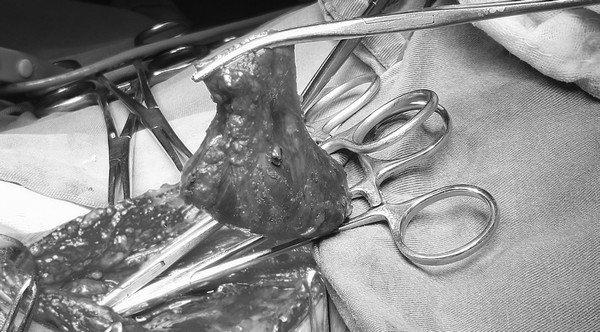

瘤体与颈内静脉血管沟通

切除后的血管瘤

手术如期进行,王兵教授亲自主刀,崔文军副主任作为助手。刚刚切开患者的表皮即看见蓝色的瘤体,因为平卧时瘤体充血,显得特别大,手术必须非常谨慎,瘤体稍有损伤即血流不止,难以控制。王兵教授凭借着熟练的手法、精细的操作,崔文军副主任密切配合,顺利地将瘤体分离,瘤体的的底部有三个部位与颈内静脉连接,如果手术中操作不慎,就有可能导致患者颈内静脉撕裂甚至扯断,后果不堪设想。王兵教授凭借丰富的经验,细心地将这三个部位分离出来并结扎,完整保留了右侧颈内静脉,手术非常顺利,出血量不足100ml。颈部皮肤缝合后进行双下肢静脉曲张治疗,采用大隐静脉剥脱结合激光治疗手段,将患者双下肢曲张血管完美的处理,创伤小,治疗彻底,而且美观。